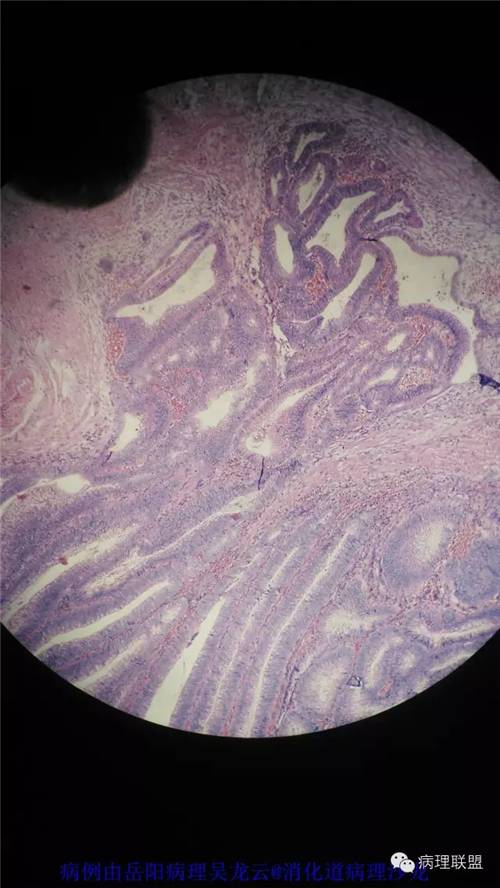

病例2

女性,60岁,结肠腺瘤活检。有一灶腺体突破粘膜肌,腺体无明显异形。

(注:病例由岳阳病理吴龙云提供 致谢!)